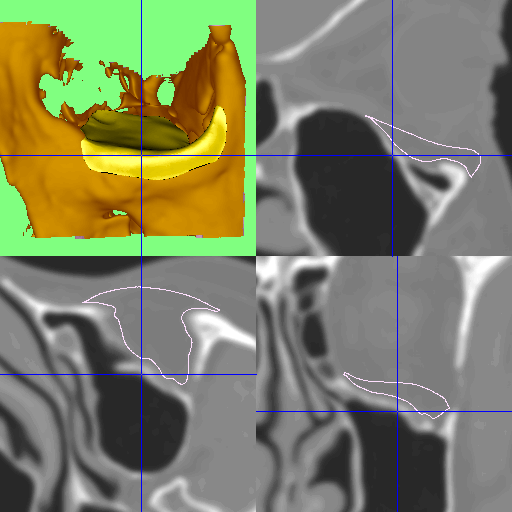

Accurate diagnosis is crucial for determining the type and extent of the fracture. A specialist will begin with a physical examination of the eye and its movements, followed by vision testing. Imaging plays a central role, with CT scans providing the most precise information about both bone and soft tissue damage. Specialist consultation with an ophthalmologist or oculoplastic surgeon is often arranged to ensure that the health and function of the eye are thoroughly evaluated.